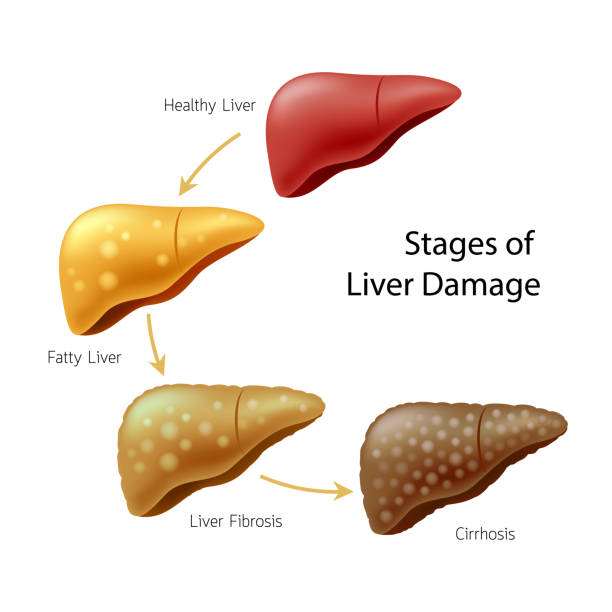

Stages of Liver Damage, Illustration – Stock Image – C027/6479 …

Stages of liver damage. Starting from a healthy liver (top left Stock …